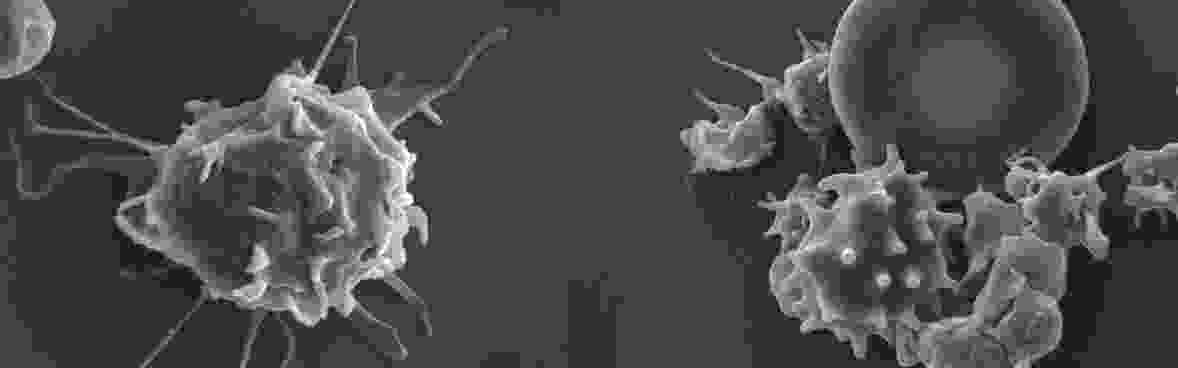

• Platelets and Leukocytes During Infection

• Platelet-leukocyte Interactions During Infection